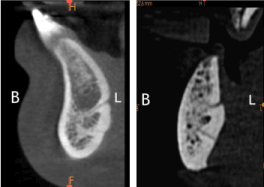

Figure 1. Anatomical location of lingual foramen

Figure 2. Anatomical location of lingual canals

Figure 8. Lingual foramen(LF) measurements

1. LF – Alveolar crest distance.

2. LF – inferior cortex distance.

3. LF – Buccal plate distance.

Figure 9. MEASUREMENTS AT BUCCAL END OF LINGUAL CANAL

1. Buccal end of LC – Alveolar crest distance.

2. Buccal end of LC – inferior cortex distance.

3. Buccal end of LC – Buccal plate distance.